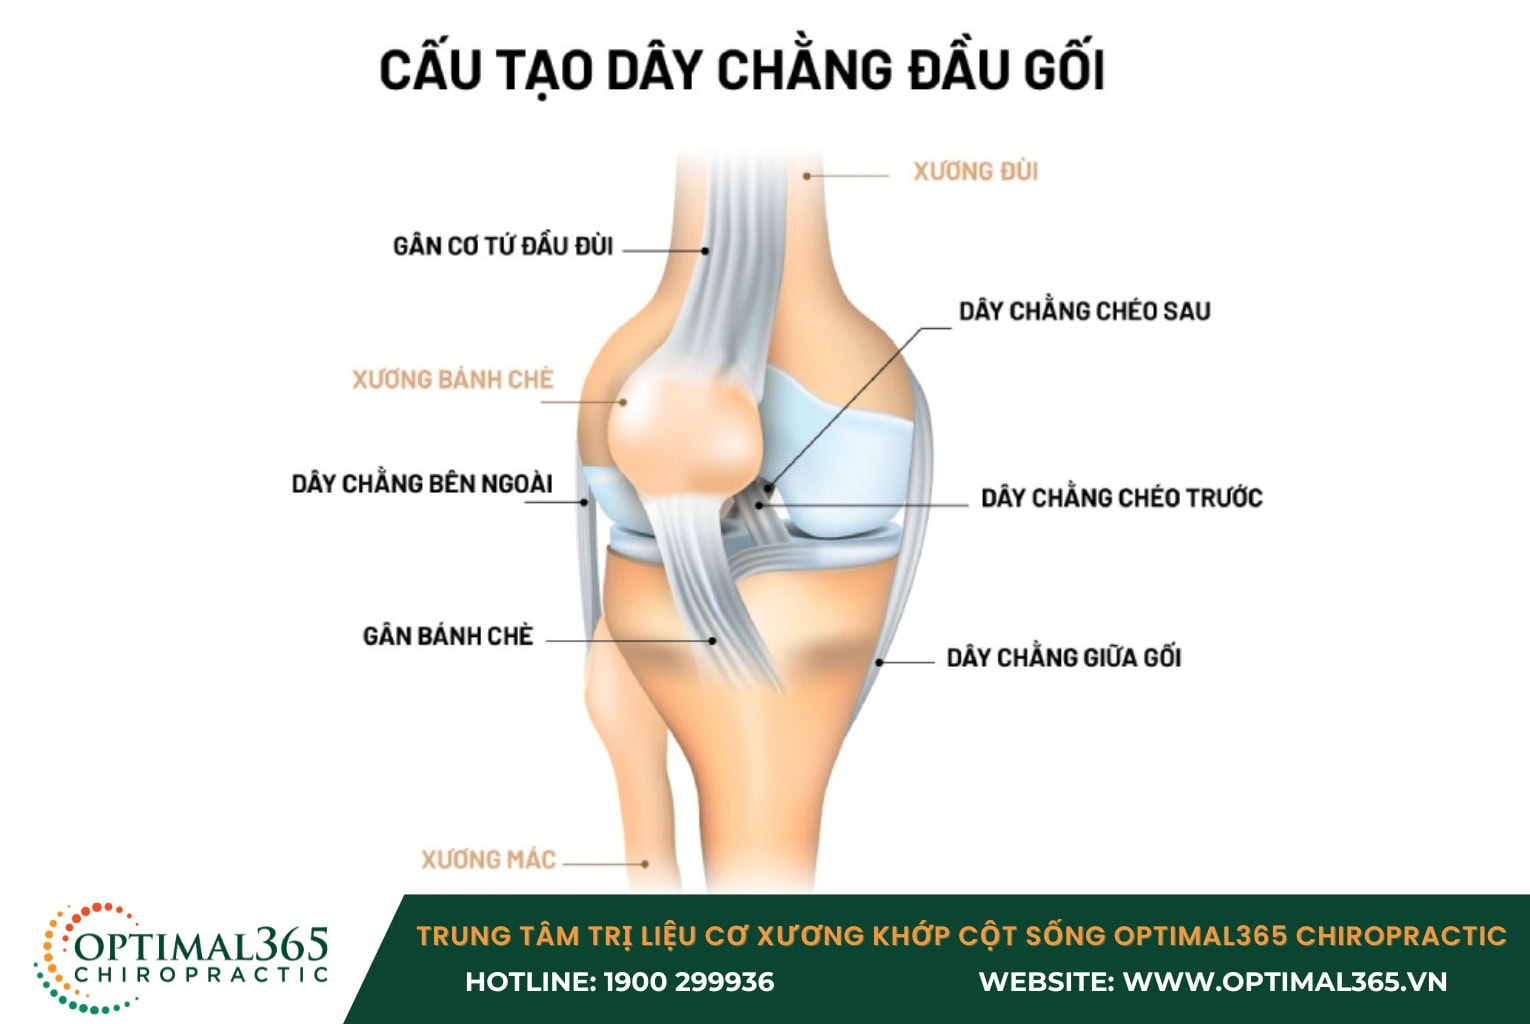

Tổng quan về cấu tạo của dây chằng đầu gối

Khớp gối là một cấu trúc phức tạp, gồm nhiều thành phần chính như xương lồi cầu đùi, mâm chày, xương bánh chè và các lớp sụn bao quanh đầu xương.

Về mặt chức năng, h ệ thống gân, cơ và dây chằng đóng vai trò quan trọng trong việc giữ cho khớp gối ổn định, có khả năng chịu lực và đàn hồi lớn, từ đó hỗ trợ các hoạt động vận động diễn ra trơn tru.

Hệ thống dây chằng của khớp gối bao gồm:

- Dây chằng chéo trước (ACL): Nằm ở trung tâm khớp gối, có vai trò kiểm soát sự chuyển động xoay và di chuyển về phía trước của xương chày, giúp khớp gối duy trì sự ổn định.

- Dây chằng chéo sau (PCL): Vị trí phía sau khớp gối, kiểm soát chuyển động lùi về sau của xương chày.

- Dây chằng giữa gối (MCL): Kéo dài từ mặt trong của đầu trên xương chày lên mặt trong của đầu dưới xương đùi, giúp ổn định mặt trong của cẳng chân.

- Dây chằng bên ngoài (LCL): Nằm ở phía ngoài của khớp gối, tạo thành một góc hẹp phía sau, có nhiệm vụ giữ vững mặt ngoài của đầu gối.